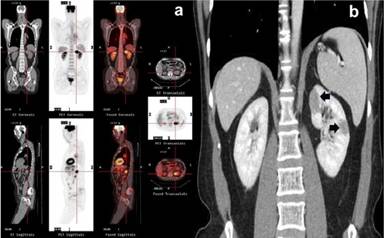

Figure 9. Composite PET/CT (a. crosshair) and coronal CT (b. arrows) show lesions of the left kidney. Case#2. |

Figure 11. Serial coronal and sagittal pre- (a.) and post-corticotherapeutic (b.) PET maximum intensity projection (MIP) images show complete resolution of the diffuse hypermetabolic lesions of systemic IgG4-related sclerosing disease. The focus at the left upper anterior chest wall represents an artifact (b.). Case#2. S: salivary glands; T: thyroid gland; H: bilateral hilar nodes; L: right middle pulmonary lobe; K: upper pole of the left kidney; P: pancreas; PR prostate |